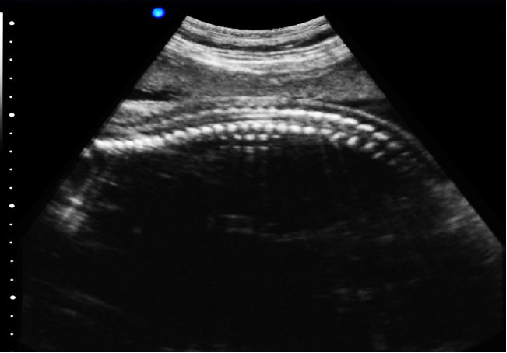

P5-VET獸用彩超機脊椎檢查圖

脊椎檢查:

脊柱裂的預防和確診,一般在動物懷孕以后定期給動物做超聲檢查,通過超聲、超聲檢查可以早期發現動物胎兒是否合并了脊柱裂或是神經管閉合不全。